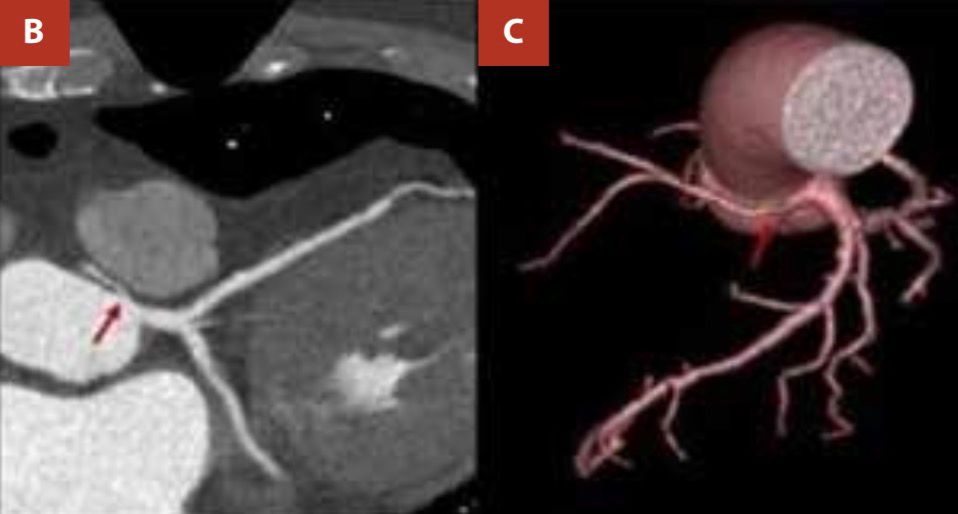

El feocromocitoma es un tumor neuroendocrino productor de catecolaminas cuya presentación clínica puede simular un síndrome coronario agudo y representar un reto diagnóstico en la cardiología clínica. Presentamos el caso de un varón de 63 años con dolor precordial intermitente, hipertensión paroxística e incremento leve de troponinas. Fue referido a nuestra institución con diagnóstico de síndrome coronario agudo. Los electrocardiogramas de ingreso no evidenciaron signos de isquemia aguda; el ecocardiograma transtorácico no mostró trastornos segmentarios de motilidad. Se propuso una estratificación isquémica no invasiva. Previo a la angiografía coronaria por tomografía computarizada (CCTA), se administró propranolol, tras lo cual el paciente desarrolló crisis hipertensiva y dolor precordial. El mismo episodio se presentó luego de una segunda dosis de betabloqueador. La CCTA no identificó estenosis coronarias significativas. Ante la sospecha de feocromocitoma, la tomografía abdominal con contraste mostró un nódulo suprarrenal izquierdo y en la orina se identificaron metanefrinas elevadas. Se realizó una adrenalectomía y la histopatología confirmó un feocromocitoma benigno. El paciente evolucionó favorablemente, asintomático hasta la fecha.